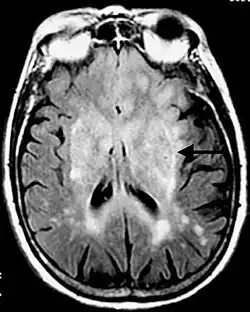

La séquence en inversion-récupération consiste à effectuer une impulsion RF à 180° dans le plan longitudinal avant d'effectuer une séquence écho de spin. Ce type de séquence est notamment utile pour obtenir un meilleur contraste entre les tissus ou bien la suppression du signal de certains tissus comme par exemple le LCR dans la Fluid-attenuated inversion recovery (séquence FLAIR)[3] ou de la graisse dans la séquence STIR (Short Tau Inversion Recovery)[4].